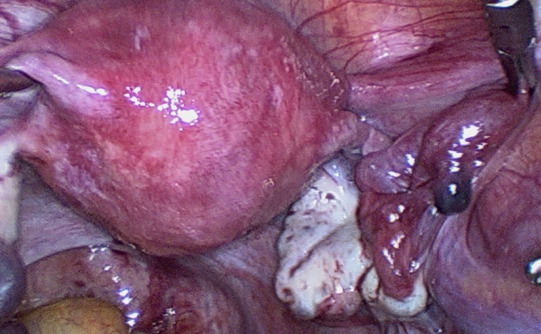

Materials and methods: The investigation was carried out in five medical centres in China and France from February to July 2021 and included reproductive-age patients who underwent gynaecological laparoscopy. Subtle abnormalities included Hydatid of Morgagni (HM) , fimbrial agglutination, tubal diverticula, accessory ostium, fimbrial phimosis, and accessory fallopian tube.

Results: 642 patients were enrolled in the study and 257 (40.0%) were diagnosed with subtle tube abnormalities. Hydatid of Morgagni was the most common abnormality (22.7%; n=146), followed by fimbrial agglutination (19.8%; n=127), tubal diverticula (6.9%; n=44), accessory tube (2.0%; n=13), and tubal accessory ostium (1.9%; n=12). Fimbrial phimosis was the least common abnormality (0.3%; n=2). The prevalence of subtle fallopian tube abnormalities was significantly higher among infertile patients (188/375, 50.1%) than those without history of infertility (69/267, 25.8%, ᶍ2=38.332, P=0.000). 209 patients were diagnosed with endometriosis during surgery, and the prevalence of subtle abnormalities was significantly higher in the endometriosis group than in those without endometriosis (61.2%, [128/209] vs. 29.8% [129/433], ᶍ2=58.086, P=0.000).

Abstract Image